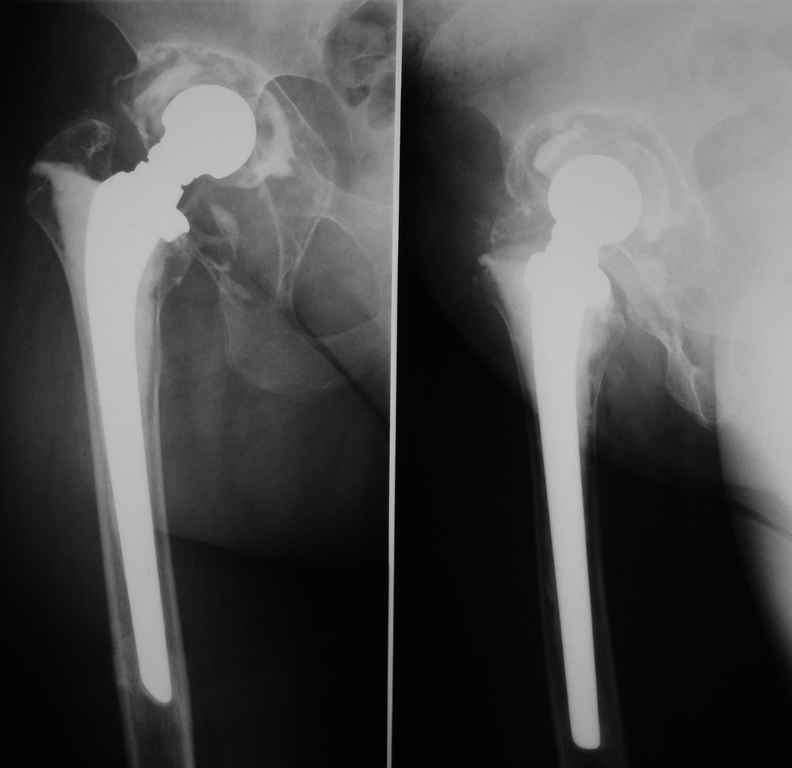

Больная 40 лет, поступила в отделение с диагнозом: Нестабильность чашки цементного эндопротеза Мовшовича правого тазобедренного сустава с протрузией тазового компонента.

An.morbi: В 1991 г.ДТП, получила ушиб правого тазобедренного сустава, после чего стали беспокоить периодические боли в правом тазобедренном сустав при нагрузке. В 1992 г. Госпитализирована в ГВКГ им. Бурденко с артрозо — артритом правого тазобедренного сустава, предположительно туберкулезной этиологии, в течение года получала спецефическую терапию (стрептомицин, тубазид, рифацин, канамицин, пиразинамид) Туберкулезный процесс перешел в стадию затихания с формированием метатуберкулезного фиброзного анкилоза, БК- (минус). В 1993 г эндопротезирование правого тазобедренного сустава цементным эндопротезом Мовшовича. Послеоперационный период протекал гладко, получала курс восстановительной терапии. В 2004 г. снята с учета в туберкулезном диспансере. В конце 2004 года появились периодические боли в правом тазобедренном суставе при физической нагрузке. С 2005 г. ходит с тростью.

Рентгенограммы от 07,07,2009г.

Данных за нестабильность ножки не выявлено.